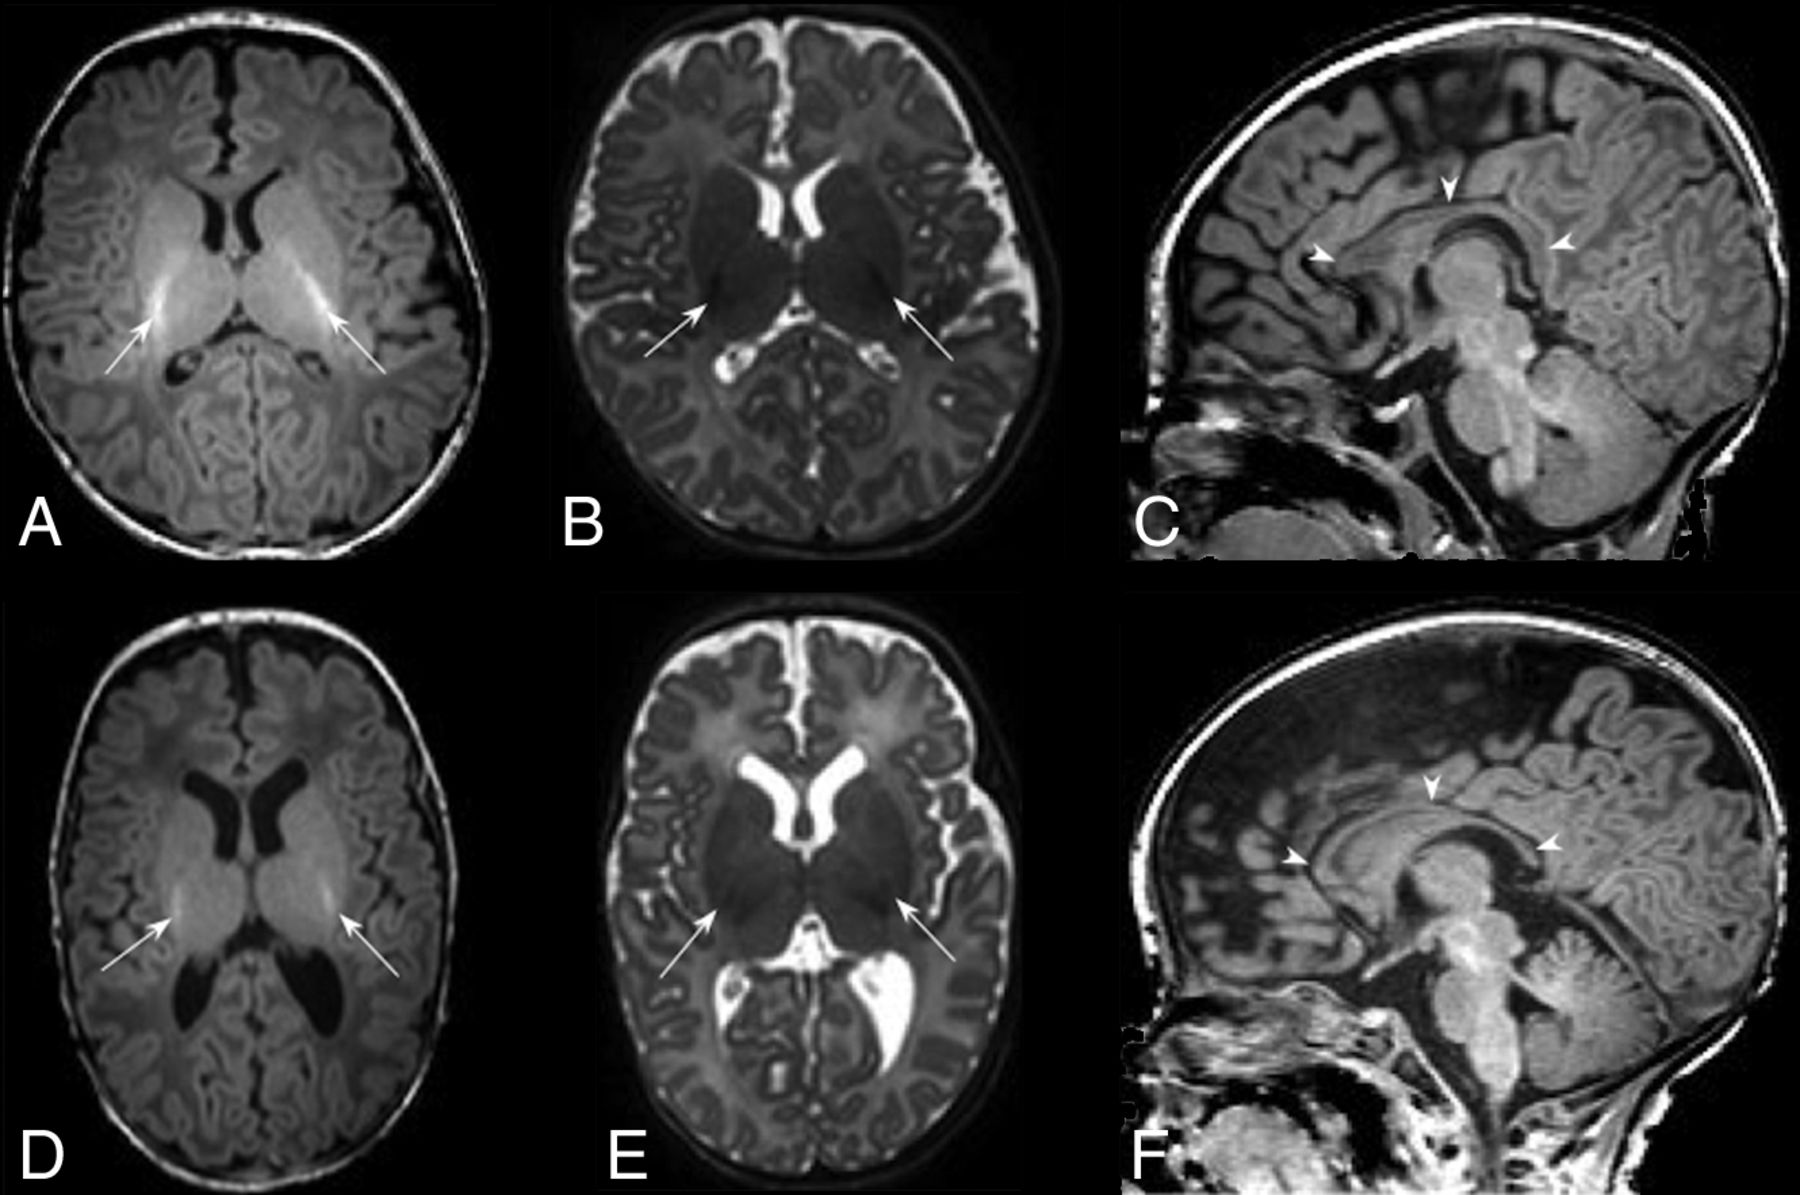

Development of the brain is known to be altered by preterm delivery. Studies have previously documented reduced cortical folding, diffuse excessive high T2 signal intensity in the white matter, and a scaphocephalic head shape (Fig 1).10 We graded corpus callosal thickness as either normal, focal, or global thinning (On-line Fig 1). Ventricular dilation was graded as absent, moderate, or global enlargement of a moderate-to-severe nature (On-line Fig 2).

Typical MR imaging brain appearances of term-born and preterm infants, at TEA. Axial T1-(A) and T2- (B) and sagittal T1 (C)-weighted images of a term-born infant (40 weeks’ gestational age) imaged at 44 weeks PMA. Note the high-T1/low-T2 signal within the PLIC from the myelin (arrows, A and B); the complex cortical folding; small, symmetric ventricles; and the typical appearance of a normal corpus callosum (arrowheads, C). By comparison, D–F are comparable images obtained from an infant born at 25 + 2 weeks’ gestational age and imaged at 42 + 4 weeks’ PMA. This infant had no acquired focal lesions however, note the scaphocephaly, reduced cortical folding, globally thinned corpus callosum (arrowheads, F), mildly dilated ventricles, and diffuse high-T2/low-T1 signal in the white matter compared with the term infant. There is grossly normal myelination in the PLIC (arrows, D and E).

Myelin within the posterior limb of the internal capsule (PLIC) is readily identifiable in the neonatal brain; absence or marked asymmetry was considered pathological (Figs 1⇓–3).